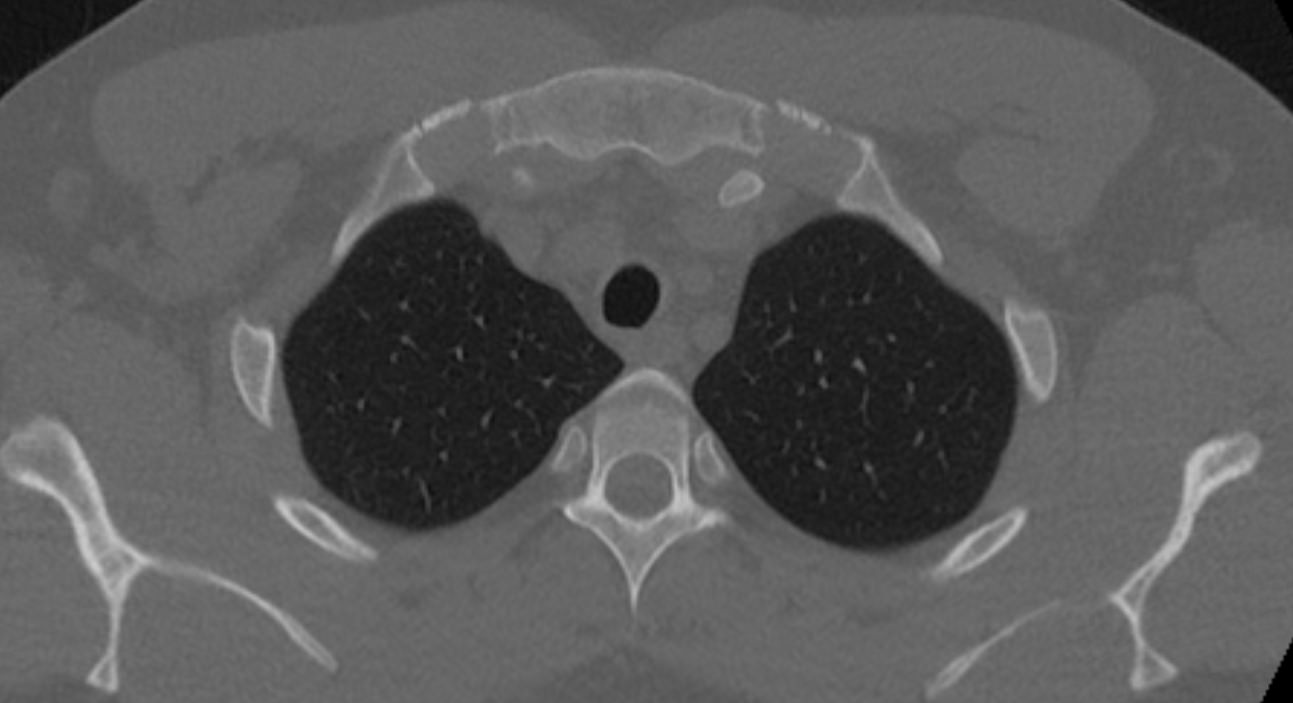

Мультиспиральная компьютерная томография ребер проводится в рамках протокола КТ органов грудной клетки. Грудина, ребра, грудной отдел позвоночника составляют костный каркас грудной клетки и при проведении КТ оценивается наличие деструктивных изменений в этих костных структурах.

КТ ребер является быстрым безболезненным высокоточным методом обследования костных структур грудной клетки. Метод позволяет получить детальные снимки и трехмерные цифровые изображения костно-мышечного каркаса грудной клетки. КТ широко используется в хирургии и травматологии при планировании оперативного вмешательства и в дальнейшем помогает оценить результаты проведенной операции.

Помимо этого, мультиспиральная КТ позволяет оценить состояние легких, трахеи, бронхов, изучить строение сердца и крупных сосудов, выявить патологию пищевода и лимфатических узлов средостения.